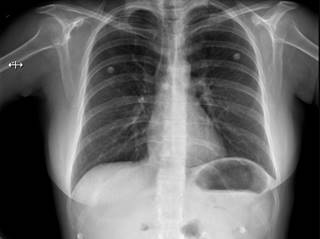

Una mujer de 47 años de edad sin antecedentes médicos se sometió a cirugía endourológica programada. Al ingreso a quirófano, se encontraba en buen estado general, con signos vitales y exploración física normales. Se aplicó anestesia general balanceada, realizando inducción con fentanilo, propofol, rocuronio y durante laringoscopia sin evidencia de anomalías. Orotubación se realizó sin complicaciones al primer intento con hoja número 3 y tubo número 7, cursa hemodinámicamente estable, sin necesidad de apoyo vasopresor con solución Hartmann intravenosa a 20 mL/h sin necesidad de mayor reanimación hídrica, ventilación de protección tidal, mantenimiento con sevorane y fentanilo en infusión calculado a 2 μg/kg/h, ventilación pulmonar simétrica y valores adecuados en capnografía postintubación. Durante el procedimiento quirúrgico sin aumento de presiones o desacoplamiento a ventilación mecánica. La paciente presentó agitación espontánea al recobrar conciencia realizando esfuerzos inspiratorios importantes con laringoespasmo breve de cuarenta segundos. La extubación presentó disminución de agitación y sin deterioro del patrón respiratorio; durante la hora de vigilancia postoperatoria, sin deterioro cardiorrespiratorio. Sin embargo, dos horas posteriores a extubación, la paciente mostró signos de dificultad respiratoria: taquipnea, uso de musculatura accesoria, desaturación al 70% al aire ambiente, estertores crepitantes bilaterales; radiografía de tórax portátil reveló evidencia de edema agudo pulmonar (Figura 1). La administración de oxígeno suplementario logró aumentar saturación hasta 92%. Ante sospecha de edema pulmonar de presión negativa, se realizaron ecocardiograma transtorácico y angiotomografía de tórax, sin evidencia de falla cardiaca ni tromboembolia pulmonar. Se optó por utilizar puntas nasales de alto flujo, diurético de asa, nebulizaciones con β-agonistas y terapia pulmonar. La paciente evoluciona de manera satisfactoria (Figura 2), dándose de alta al tercer día postoperatorio.

Figura 1: Radiografía de tórax anteroposterior. Edema agudo pulmonar.